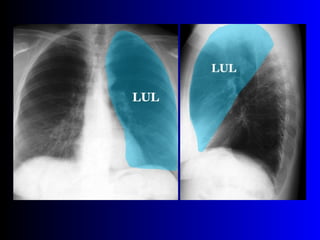

Este documento describe la técnica para realizar una telerradiografía de tórax normal e identifica las estructuras visibles en la imagen, incluyendo los huesos, vasos sanguíneos, grasa, tejido subcutáneo, pulmones y mediastino. Explica que es importante centrar la imagen en los ápices pulmonares, senos costodiafragmáticos e inspiración profunda para una visión clara de las estructuras.